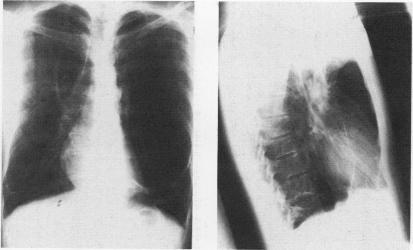

A routine chest radiograph in a 20 year old man revealed a giant air filled cavity of the left hemithorax under tension. At thoracotomy a large left lower lobe intraparenchymal cyst required lobectomy and the pathological findings were consistent with a bronchogenic cyst. Although tension bronchogenic cysts are common in infants, this case demonstrates their unusual presentation in an adult.